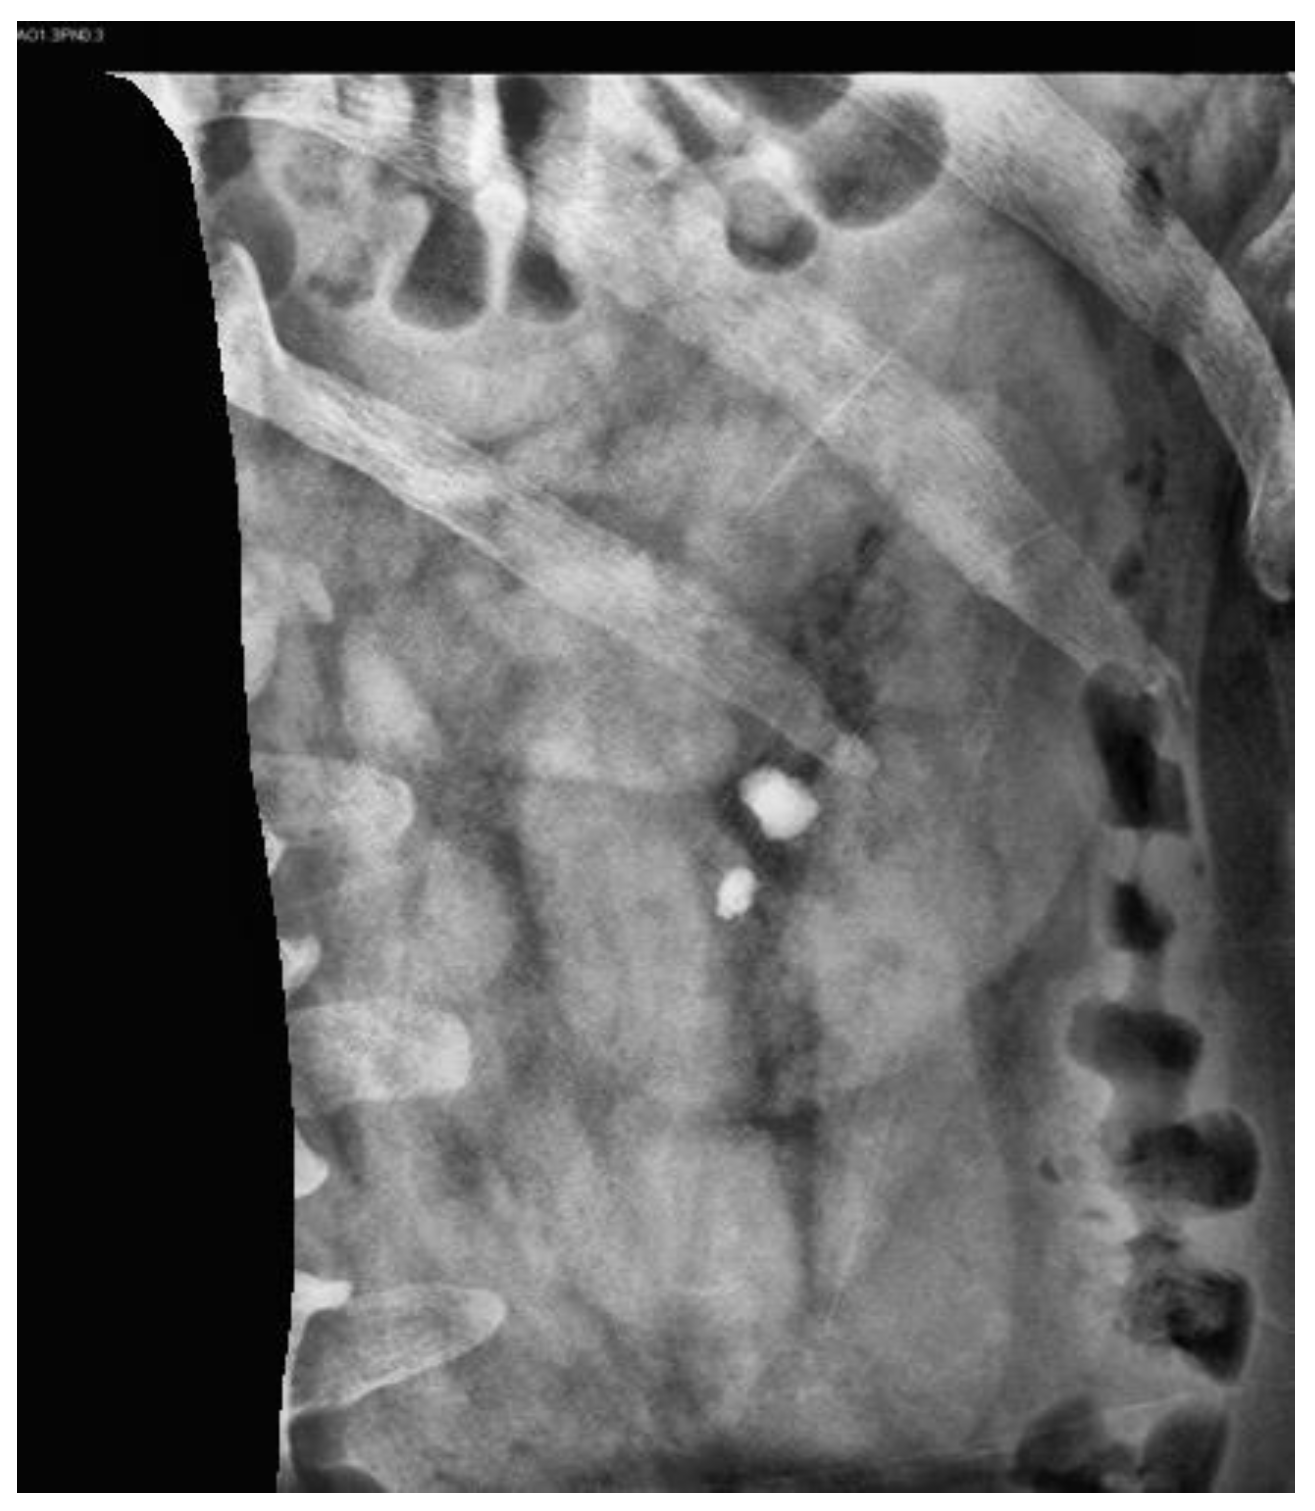

2.3. Image Preprocessing

2.3.1. Contrast-Limited Adaptive Histogram Equalization

2.3.2. Image Mask

2.3.3. Image Cropping